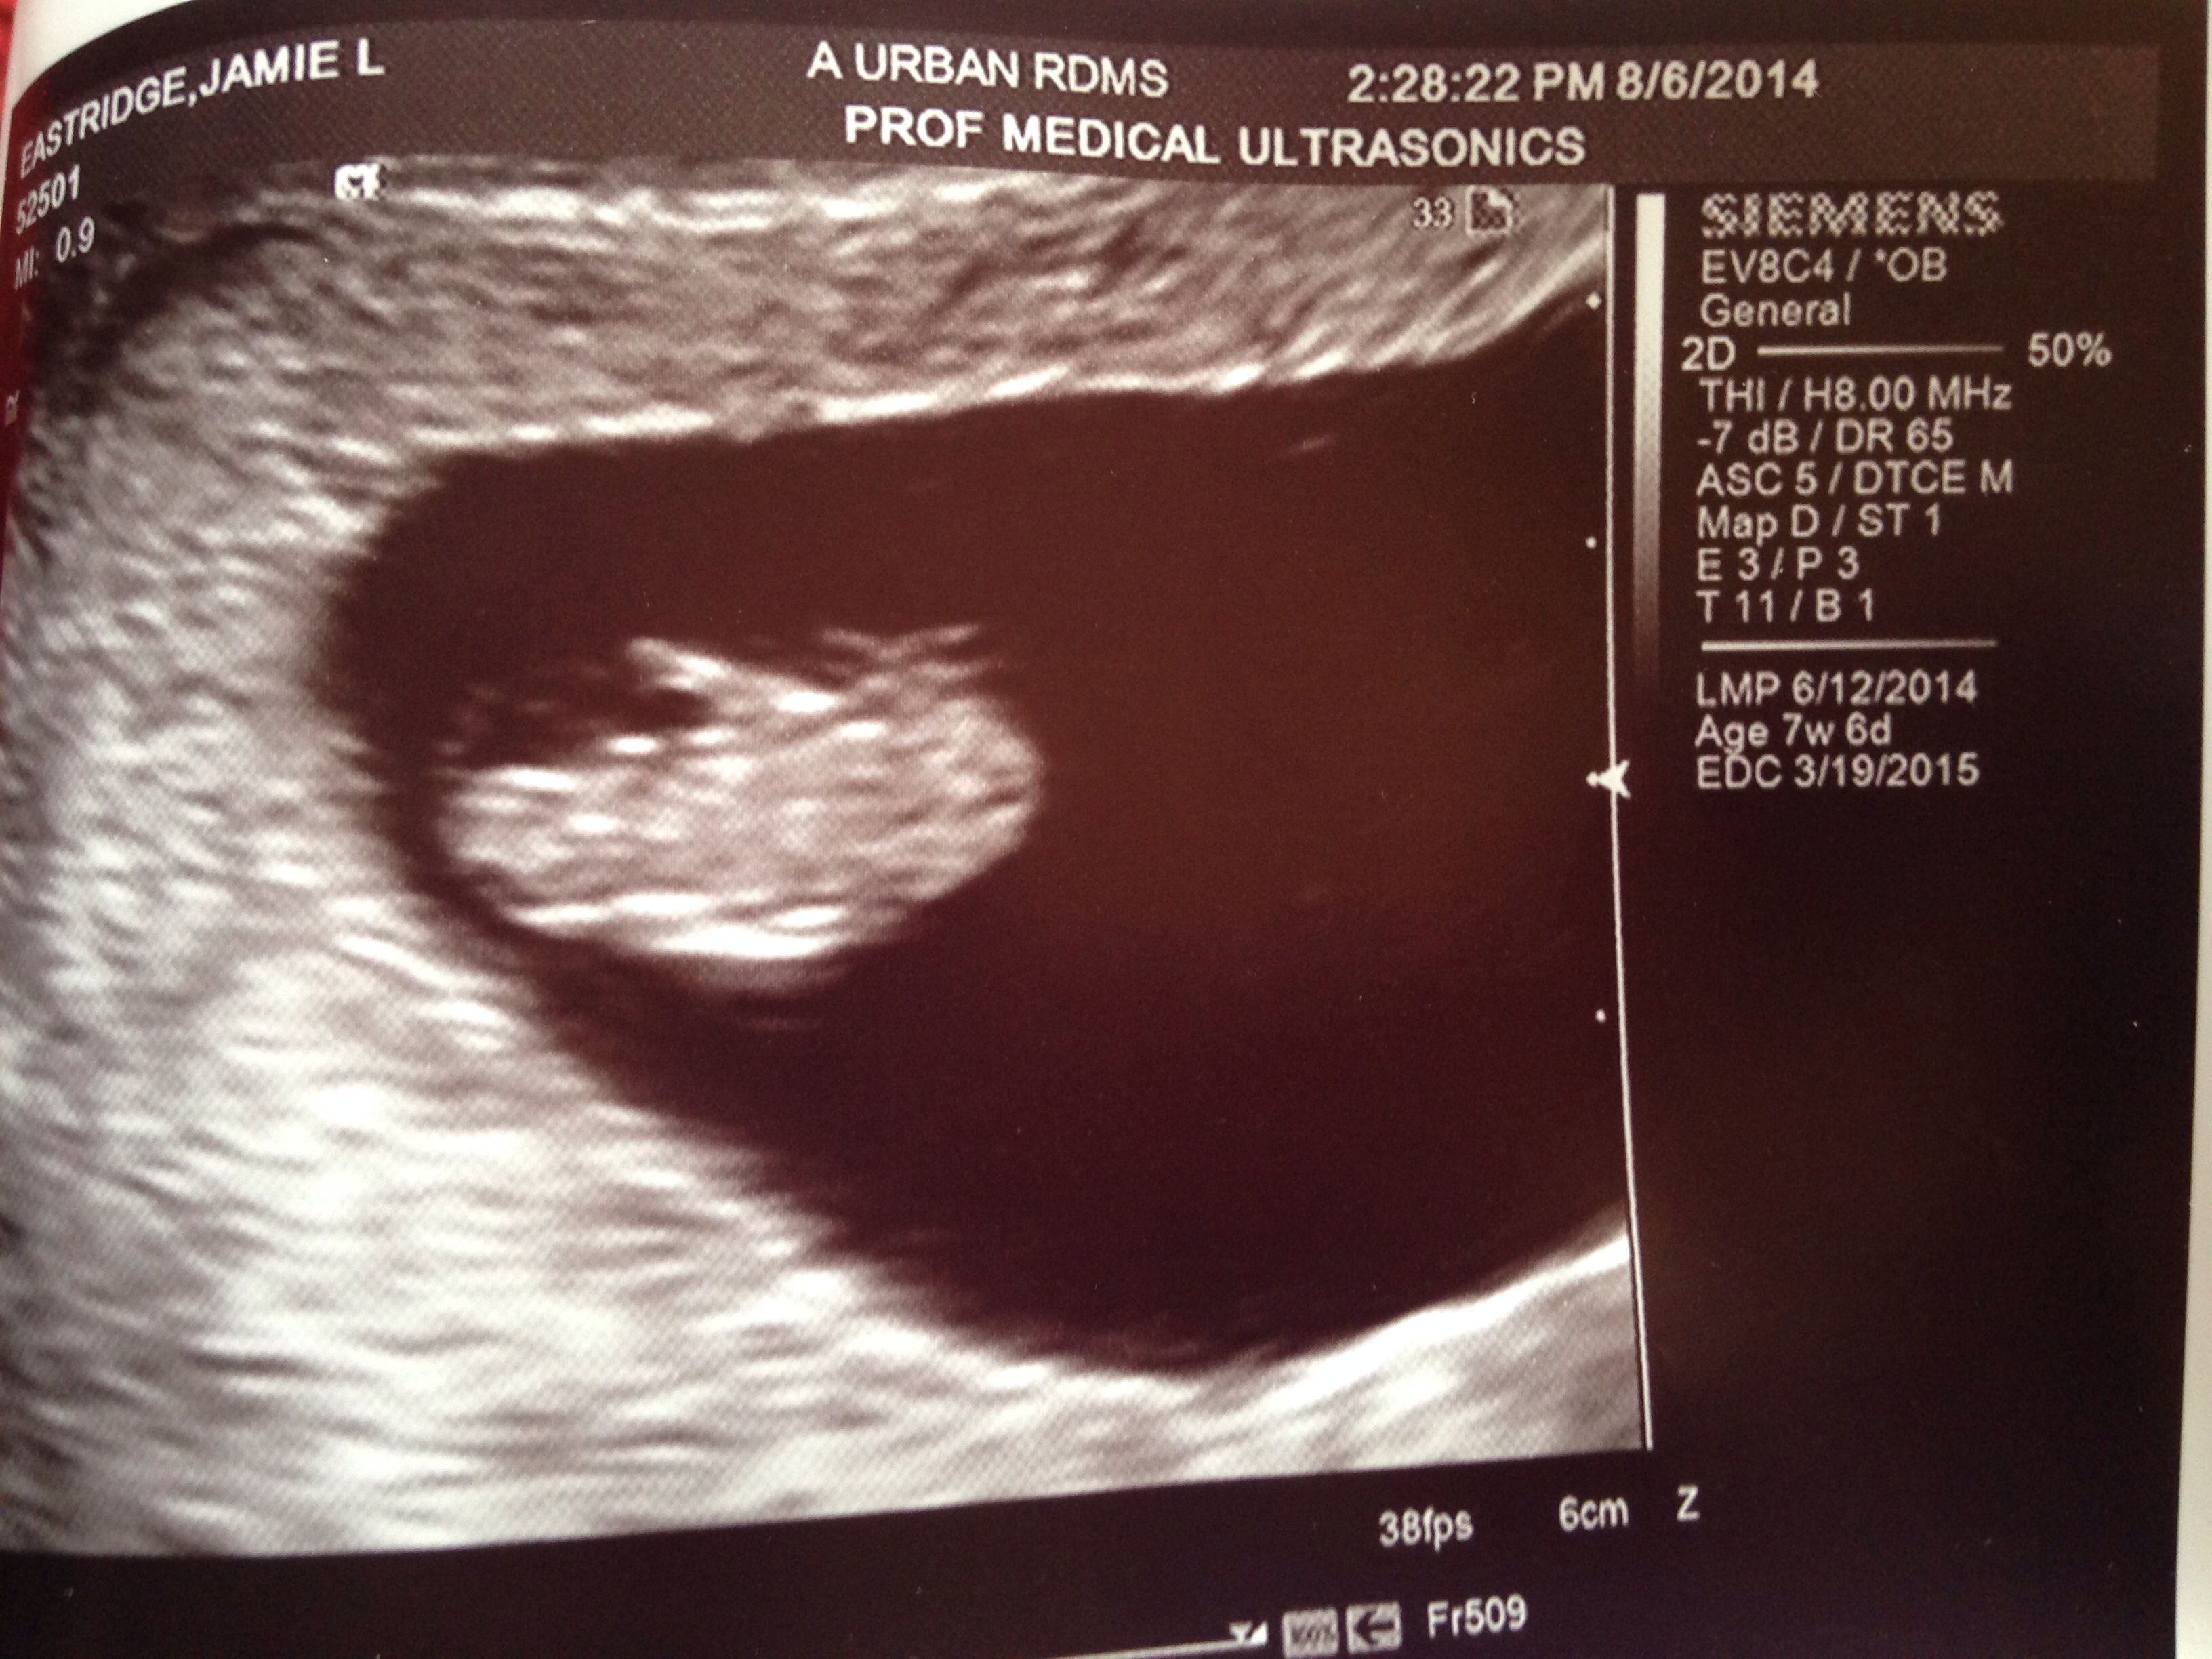

Finally got in for an u/s today...and thank God we have a LO with a strong HB of 140 at 7w6d...have a large cyst and my uterus it flipped backwards but they aren't concerned...I'm just too happy!!!!

Re: Finally...an u/s...and a HB!!!!